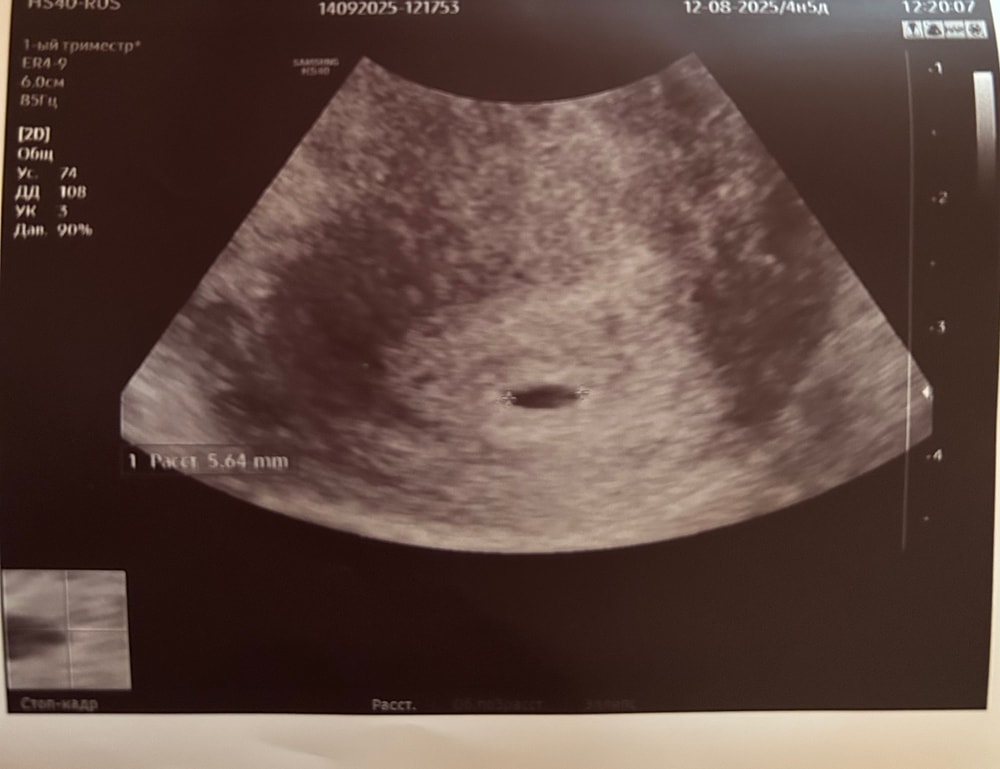

УЗИ, КТГ, доплерСо вчерашнего УЗИ не нахожу себе места.

ПЯ 5 мм

вытянутое

срок по месячным 4.5 нед